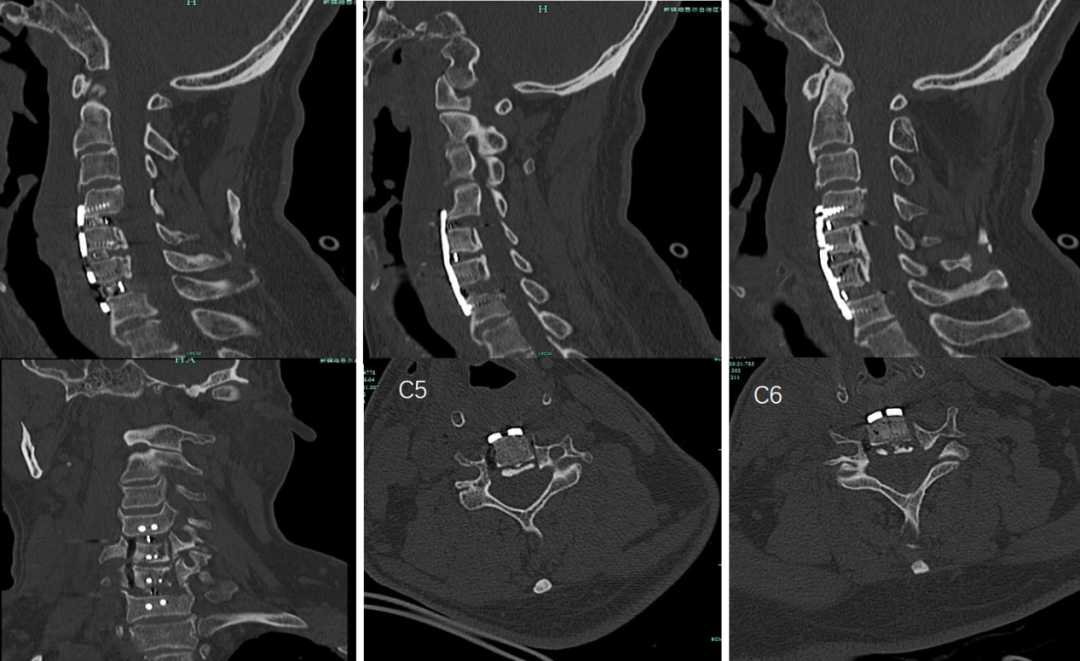

术后CT: